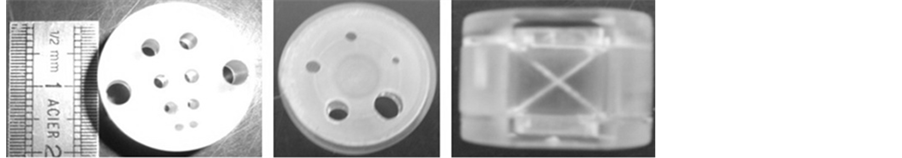

Following the fixed design and using Plexiglas cylinders with a diameter of 3 mm, the proposed phantom is realized (Figure 3). It is composed of the following:

・ The phantom body that is a cylindrical enclosure with a sealed cover and two holes for the introduction of

Figure 3. Patterns contained in the phantom (a) Spatial linearity (micro-PET, micro- SPECT, micro-CT); (b) Hounsfield unit linearity (micro-CT); (c) Spatial resolution and diffusion profile (micro-CT); (d) Spatial resolution (µPET, micro-SPECT); (e) Low contrast detectability (micro-CT); (f) Slice thickness (micro-CT).

solutions with contrast agents (Figure 4). The patterns for control of various performances are housed in the cylinder.

・ The pattern of spatial linearity, which is in the form of a solid cylinder in which we have made orthogonal and periodic grooves 1.5 mm wide, 3 mm deep and spaced 1.5 mm (Figure 3(a)).

・ The pattern of Hounsfield unit linearity that consists of four cylinders of the same size and which Hounsfield units are indexed by the manufacturer: the first is filled with water (~0 HU), the second is filled with polyethylene (~+80 HU), the third is filled with teflon (~+1000 HU) and the fourth is filled with air (~−1000 HU) (Figure 3(b)).

・ The pattern of spatial resolution and the diffusion profile for micro-CT that contains a copper wire 0.2 mm thick elongated parallel to the axis of the phantom and a prismatic needle with a square base (2.5 × 2.5 mm2) (Figure 3(c)).

・ The pattern of spatial resolution of micro-SPECT and micro-PET shows as a solid cylinder in which we operated four pairs of holes with diameters of 1, 1.5, 2 and 2.5 mm (Figure 3(d)).

・ The pattern of low contrast detectability that is made of two disks 0.5 and 1 mm thickness in which are pierced in the same position five holes of diameters 1, 1.5, 2, 3 and 4 mm (Figure 3(e)).

・ The pattern of slice thickness measurement in micro-CT that consists of two opposite ramps of aluminium with a thickness of 0.6 mm and an inclination angle q of 25.36˚ (Figure 3(f)).